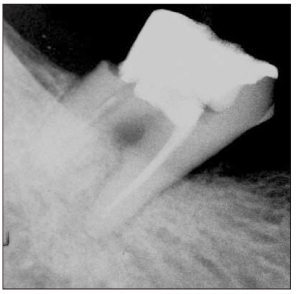

Figure 1

Diagnostic intraoral radiograph (a). Separated file in the mesial root isthmus (b, c) and remove it using ultrasonic device under microscope (d).

Figure 1 Diagnostic intraoral radiograph (a). Separated file in the mesial root isthmus (b, c) and remove it using ultrasonic device under microscope (d).